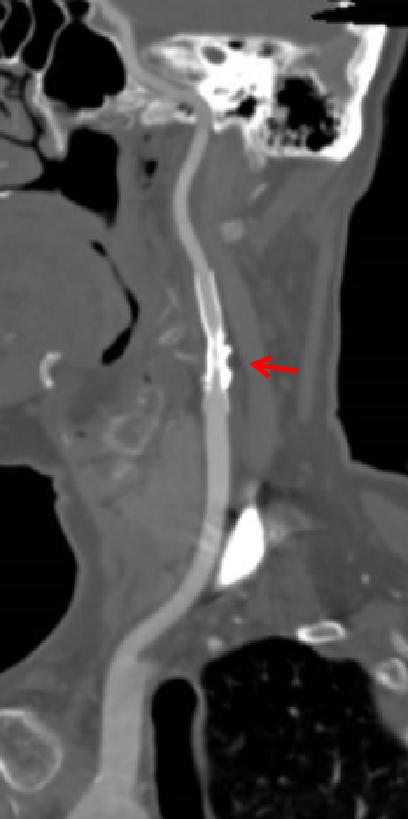

研究将颈动脉支架术分为四个阶段:小球囊预扩张、大球囊预扩张、支架放置、球囊后扩张。发现只有大球囊预扩张时的血流动力学不稳最显著,支架放置和球囊后扩张对血液动力学不稳的影响较小。

安贞医院血管外科